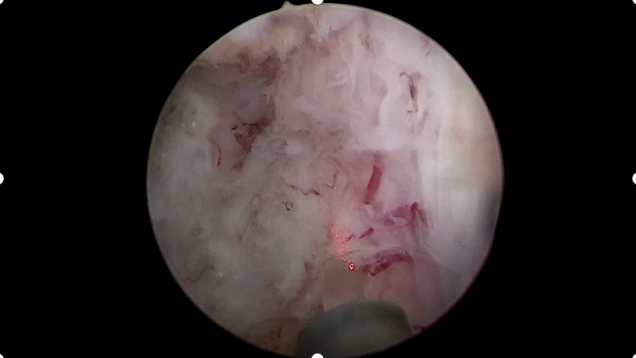

1月28日,贵州航天医院第94次晨读会由我院泌尿外科主治医师娄进作学术交流,他以“神经刺激在膀胱过度活动症(OAB)中的应用”为题,详细讲解了该病症的临床表现、发病机制及治疗策略等内容,并结合实际案例图文介绍了骶神经刺激、经皮胫神经刺激等调节技术的实际应用场景与操作特点,为相关症状的临床管理提供了理论与实践参考,拓展了治疗思路。 贵州航天医院 泌尿外科专家简介 石 英 泌尿外科党支部书记、主任,主任医师 中国医师协会泌尿外科分会感染协作组委员,奥林巴斯泌尿系软镜西南区专家组成员,西南地区第一批输尿管软镜专家组成员,贵州省医学会泌尿外科分会委员,贵州省性学会理事,贵州省性学会常务委员,贵州省泌尿外科专业医疗质量控制中心专家委员会委员。 从事泌尿外科专业近30年,熟练掌握泌尿系各类疾病的诊治,具有丰富的临床经验,擅长泌尿系结石、腹膜后肿瘤及泌尿系肿瘤的手术治疗,对泌尿系感染、泌尿系结核、尿源性脓毒血症的救治有独到的见解及抢救经验,在贵州省率先引入输尿管软镜技术,同时在男科领域,对男性阳痿、早泄及前列腺疾病有很深的研究。 李国成 泌尿外科副主任,副主任医师 中国人体健康科技促进会男科学专业委员会委员,贵州省性学会泌尿外科分会委员,贵州省医学会男科学分会委员,遵义市医学会男科学分会副主任委员兼秘书长,遵义市医学会泌尿外科分会常务委员,贵州航天医院男科带头人。 从事泌尿外科及男科工作10余年,曾多次前往上海交通大学附属第一人民医院、中国中医科学院西苑医院进修学习男科;擅长性功能障碍的诊治、男性整形手术、前列腺增生激光手术、显微手术等。 李 凯 中共党员,泌尿外科副主任医师 贵州航天医院肿瘤腔镜组带头人,擅长肾癌根治术、输尿管癌根治术、膀胱及前列腺癌根治术、腹腔镜输尿管狭窄切除吻合术、输尿管切开取石术等手术,在遵义市率先开展泌尿系结核后膀胱挛缩全腹腔镜下膀胱扩大术。 贵州省医学会泌尿外科分会青年委员,遵义市医学会男科分会常务委员,遵义市医学会泌尿外科分会常务委员。 娄 进 中共党员,泌尿外科主治医师 贵州省医学会男科学分会前列腺组委员,遵义市医学会男科学分会常务委员。 擅长神经源性膀胱、膀胱过度活动症、间质性膀胱炎、压力性尿失禁等排尿功能障碍性疾病及女性盆底器官脱垂、前列腺增生的微创治疗。 贵州航天医院泌尿外科简介 基本情况 贵州航天医院泌尿外科创建于20世纪60年代,经过几代人的努力,微创与内镜手术占比达90%以上,科室亚专业框架完善。是贵州省临床重点专科建设单位、北京清华长庚医院李建新教授团队诊疗及会诊中心、北京医学会尿路修复与重建诊疗及会诊中心、上海公济泌尿外科集团遵义中心、上海援黔专家李铮教授男科工作室、贵州省泌尿外科质量控制专家委员单位。 专科特色 (一)泌尿系结石内镜碎石技术 泌尿系结石微创治疗领域方面是贵州省首家引进科医人钬激光碎石技术科室,在遵义地区率先掌握输尿管硬镜、软性镜,经皮肾镜钬激光碎石技术。目前是北京清华长庚医院泌尿外科“手把手”经皮肾镜碎石技术培训基地、贵州省输尿管软镜培训基地。 1.负压吸引可弯曲软镜鞘电子软镜碎石术 2.标准与超微通道相结合的经皮肾镜碎石取石术 (二)微创腹腔镜技术 泌尿外科腹腔镜技术师承于浙江省人民医院、北大、北京解放军总医院。目前采用经腹、经后腹双入路法的腹腔镜技术完成肾部分切除、肾切除、肾输尿管全长切除、肾盂输尿管成形、输尿管狭窄吻合、膀胱翻瓣等手术。在遵义地区率先掌握腹腔镜下膀胱癌根治术、腹腔镜下前列腺癌根治术。 (三)男科、盆底技术临床应用 遵义地区男科分会主委单位,是贵州省首家引进尿动力学检查并取得了全国资质认证科室,也是贵州省首家进行RigiScan检查的单位。在遵义地区率先掌握显微取精子技术以及显微镜下治疗精索静脉曲张、显微镜下输精管吻合、输精管附睾吻合技术。率先采用前列腺激光剜除术治疗前列腺增生症。在陆军军医大学西南医院泌尿外科主任沈文浩教授指导下,完成遵义市首例神经源性膀胱骶神经调节刺激器置入术。 诊疗范围 诊疗范围(除外肾移植、癌栓):泌尿系结石、泌尿系肿瘤、肾上腺疾病、肾积水、前列腺增生、男性生殖器功能障碍(精索静脉曲张、生殖道感染、输精管梗阻等)、盆底功能障碍性疾病(膀胱脱垂、排尿功能异常、尿失禁)、泌尿生殖系畸形。 泌尿外科拥有独立门诊治疗室、日间手术室、尿动力学检查室、精液分析检查室、男性勃起功能检查及治疗室、ESWL治疗室、结石分析检查室。 end